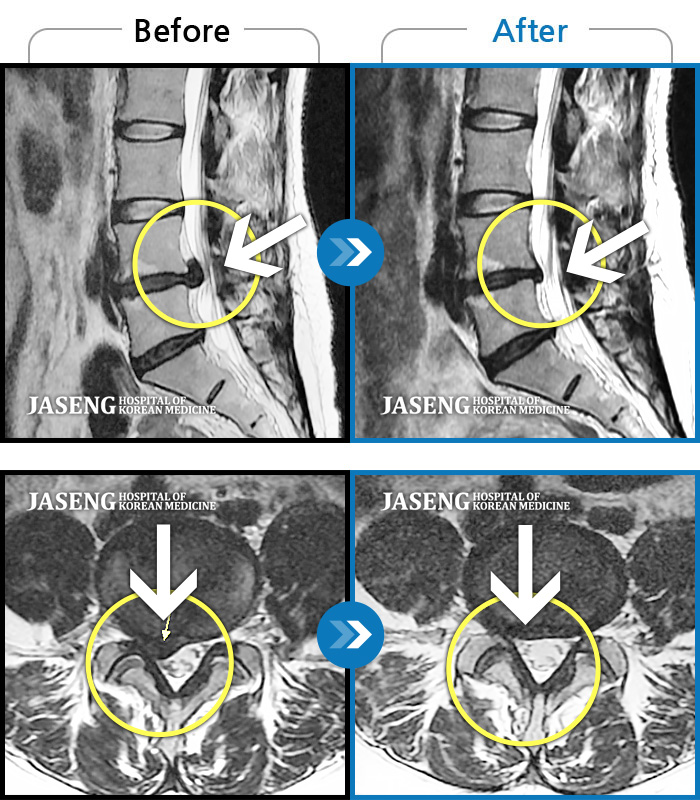

MRI 치료사례

허리디스크

목동 · 이민수 원장

오른쪽 정강이 감각이 무디고, 발바닥 통증

촬영시기

2019.07.16 ~ 2020.02.13

2020.02.21